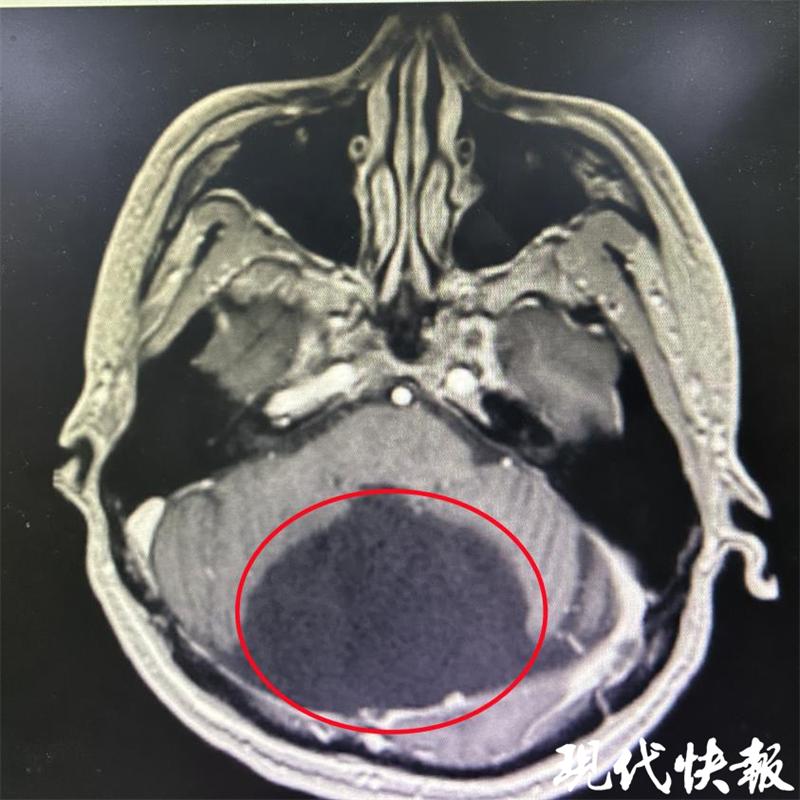

△患者颅内囊肿影像

神经外科副主任陈中俊博士为张先生详细查体后,又做了相关的辅助检查,发现他后颅囊肿约7.6*5.9cm,如果囊肿长大,不但头会更疼,严重时可能导致偏瘫,而且还有生命危险。